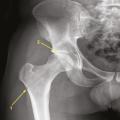

Ostéonécrose aseptique de la tête fémorale

OSTEONECROSE ASEPTIQUE

Image